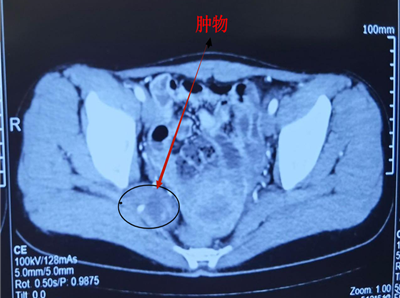

患者于3+月前跑步后出现下腹胀痛,伴轻微肛门坠胀感,休息后可缓解。2024-10-06外院经阴道三维彩超:右侧盆腔可见大小约49mm*20mm混合回声团,可见少许血流信号。全腹部增强CT:右侧盆壁(梨状肌内表面)占位,51mm*24mm,肿瘤性病变可能(如图1)。盆腔MRI检查:盆腔右侧梨状肌旁囊实性包块,约45mm*24mm。无发热,无尿频、尿急,无便秘、腹泻等改变,无下肢发麻,无下肢运动障碍;起病以来,精神、食欲可,大小二便正常,体重无明显变化。

图1 患者盆腔CT